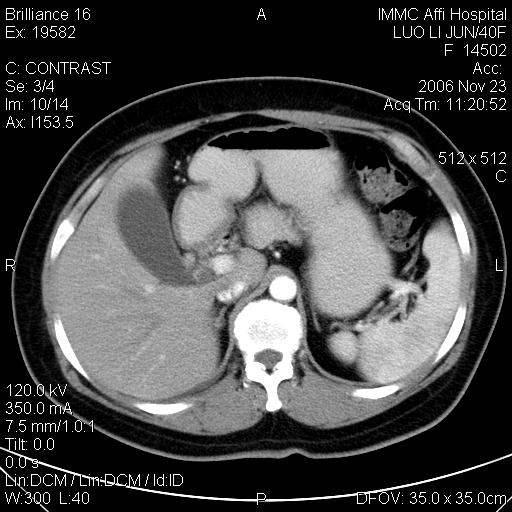

标题: CT5664:我也发一个肝脏的片子大家看看

很典型的肝癌。

速升速降,典型肝癌.

支持-----考虑肝癌----[-从片上看增强早期应该是动脉晚期即门脉早期]

是啊,典型的早出早归!

快进快出典型肝癌.

符合肝癌的增强特征。支持肝癌!

病灶好圆!可能恶性度不高。

很好的片子,可惜增强做的比较失败,a期时间没有把我好,实际到了静脉早期了,否则会更典型。

最终考虑是肝腺瘤